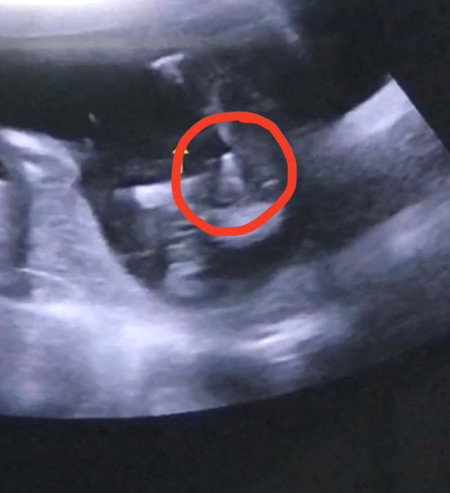

แม่ๆดูเพศน้องช่วยหน่อยค่าา 🙏🏻 น้อง 17week+6วันค่ะ ไปซาวมาวันนี้ คุณหมอบอก50/50 ค่ะ

ดูยากอยู่ค่ะ อย่างของเราเป็นแบบนี้เลย เป็นผู้ชายย 17วีคเหมือนกัน